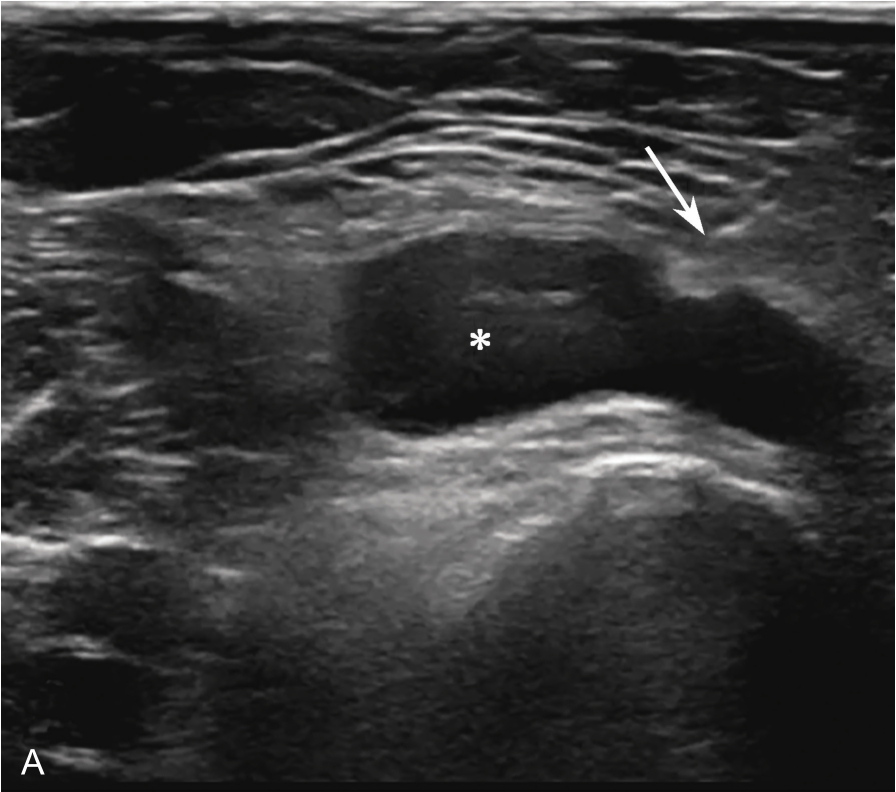

▲ 图2-1-2 肩峰下-三角肌下滑囊炎超声图

星号:肩峰下滑囊增厚伴滑膜增生